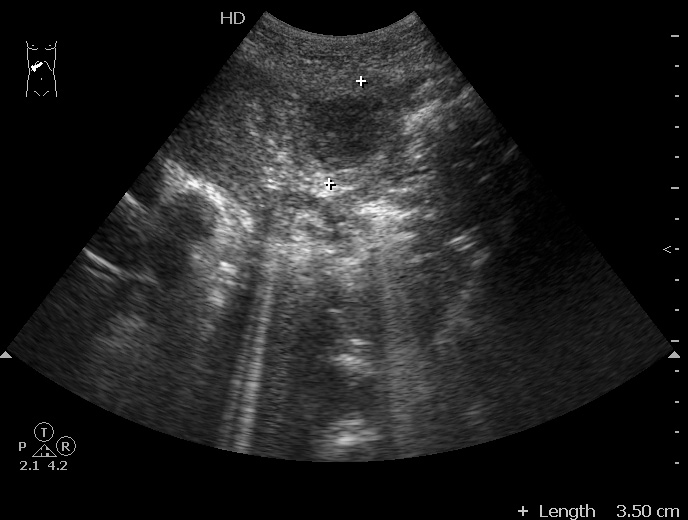

#1

06-12-05-105726_KAZACHENKO-.jpg

06-12-05-105726_KAZACHENKO-.jpg (49.5 КБ) 1448 просмотров

Типичная картина ##1-4:

Гипоэхогенное неоднородное округлое образование, окруженное эхогенным "демаркационным валом"

измененной паренхимы печени.